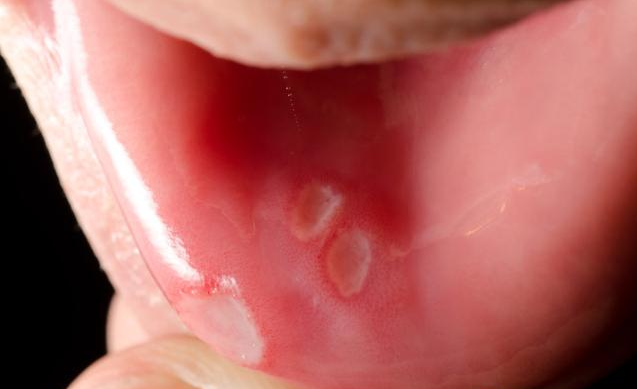

有過口腔潰瘍經歷的人都知道這個感覺是不好受的,如果口腔潰瘍長期不好,而且反反復復發作,也要注意癌變的癥狀,那么,口腔潰瘍一直不好會得口腔癌嗎?什么癥狀的口腔潰瘍要引起重視?接下來八寶網小編就來說說。

口腔潰瘍如果一直不好的話確實有可能惡化成口腔癌,尤其是那些經久不愈,大而深的舌頭潰瘍,有可能是一種癌前病損,極易癌變,所以一定要引起注意。

什么癥狀的口腔潰瘍要引起重視

首先,重復相同的傷口潰瘍

口腔潰瘍有很多種,包括復發性潰瘍和創傷性潰瘍。反復發作不是癌癥,一定要注意創傷。如果口腔總是在同一區域反復潰瘍,則可能導致口腔粘膜變成癌變。

其次,是痛苦無法忍受,潰瘍引起的疼痛程度不同。

有些人有難以忍受的疼痛,有燒灼感,明顯感覺耳朵和喉嚨疼痛。這時,我們一定要去看醫生。可能有口腔癌的跡象。

除此之外,傷口的形狀是不規則的

如果口腔潰瘍的傷口不均勻,有很多顆粒,很難觸及,整體形狀不規則,只是疼痛不那么明顯。此時我們必須警惕口腔癌。

有時口腔潰瘍發生在口腔癌之前,很容易被大家忽視,認為它是一種非常常見的潰瘍,事實上,它是口腔癌的癌前病變或癌前癥狀,其主要表現之一是口腔潰瘍,所以我們必須保持警惕。